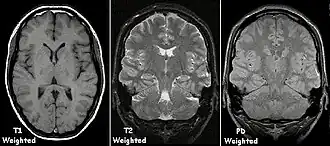

Magnetic resonance imaging (MRI) is a common form of biological data visualization used to form pictures of internal biological processes. Different settings of radiofrequency pulses and gradients result in different image appearances; these combinations are known as MRI sequences. A particularly notable subset of MRI is magnetic resonance angiography, which is a group of techniques used to image arteries and veins. MRI's imaging utility is further expanded upon by diffusion MRI and functional MRI, which can be used to capture neuronal tracts and blood flow respectively.

Diffusion MRI further relies on diffusion tensor imaging (DTI), which measures water molecule diffusion and directionality, and diffusion basis spectrum imaging (DBSI), which extracts multiple anisotropic and isotropic diffusion tensors.[39][40] Functional MRI relies on blood-oxygen-level dependent (BOLD) contrast, which measures the proportion of oxygenated hemoglobin in specific areas of the brain; this allows it to measure and model brain activity based on blood flow.[41] Further MRI techniques include saturation pulses (used to reduce motion artifacts), gradient echo (such as dynamic contrast enhancement), spin echo, and diffusion weighting (a signal contrast generation method based on differences in Brownian motion).[42][43][44]

To generate an observable image using MRI, the target is placed in a powerful magnetic field, such as that of an MRI machine. This causes the axes of the hydrogen protons inside the target, which are usually randomly aligned according to equilibrium, to be lined up in the same direction, creating a magnetic vector oriented along the magnet's axis. This orientation also allows the hydrogen protons' spin, or frequency of rotation, to be measured. The alignment is then disrupted using radiofrequency (RF) pulses (RF being a type of non-ionizing electromagnetic radiation).[45] When the magnetic field is removed, the hydrogen protons return to their equilibrium states in a process known as relaxation, and in doing so they emit RF energy.[46] Different tissues relax at different rates, which allows scientists to use specific RF pulse sequences to emphasize particular tissues or abnormalities.

After a period of time following the RF pulse, the RF energy signals emitted by the protons are measured to obtain frequency information from each location in the imaged plane. Then Fourier transformation is used to convert this frequency information into intensity levels, which are displayed as shades of grey in the generated image.

In general, two aspects of the relaxation process are measured: the time taken for the magnetic vector to return to its resting state (also known as T1 or spin–lattice relaxation), and the time taken for the axial spin of the hydrogen protons to return to its resting state (also known as T2 or spin–spin relaxation).[47] To create a T1-weighted image, the MR signal is measured by changing the amount of time between RF pulses (also known as the time to repeat, or TR). To create a T2-weighted image, the MR signal is measured by changing the amount of time between delivering the RF pulse and receiving the RF energy signals from the hydrogen protons (also known as the time to echo, or TE). The dominant signal intensities of T1 image weighting are fluid (black due to low intensity), muscle (grey due to intermediate signal intensity), and fat (white due to high signal intensity). Fat suppression is applied to many T1 weighted sequences to suppress the brightness of the signal created by it. The dominant signal intensities of T2 image weighting are fluid (white), muscle (grey), and fat (white). T2 signals are also often emphasized or suppressed depending on what the goal of the imaging is; notable examples include fat suppression, fluid attenuation, and susceptibility weighting.

Also of note are proton density (PD) weighted images, which are generated using a long TR and a short TE. PD is useful for differentiating between fluid, hyaline cartilage and fibrocartilage, which makes it ideal for imaging joints. Outside of joint imaging it has largely been replaced by fluid attenuated inversion recovery (FLAIR), an inversion recovery sequence that removes the signal from cerebrospinal fluid.[48]